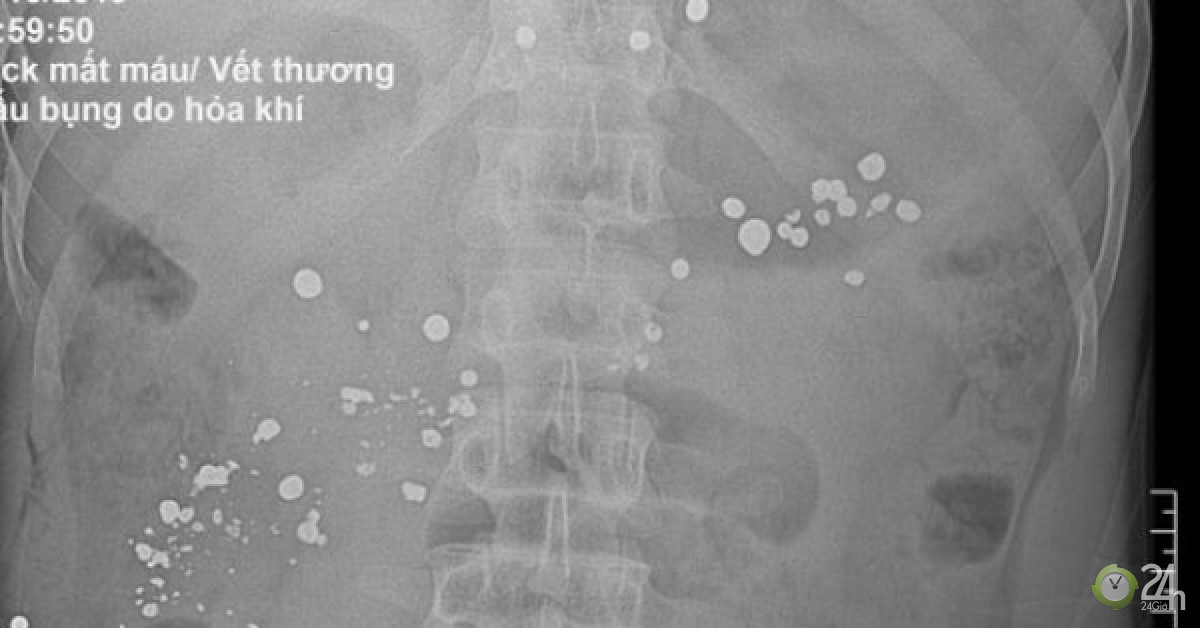

Kết quả thăm khám và xét nghiệm cho thấy, có rất nhiều dị vật kim khí cản quang trong ổ bụng, mạn sườn trái và vùng khung chậu. Bệnh nhân được chỉ định phẫu thuật gấp để bảo toàn tính mạng.